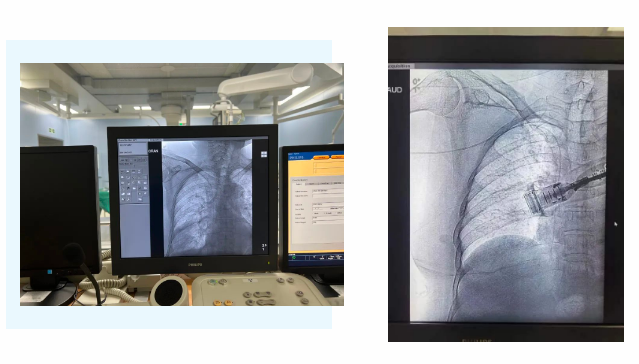

在麻醉手術(shù)中心的配合下,手術(shù)首先由韓海靜護士長在超聲引導下應(yīng)用“塞丁格”法穿刺將針尖一樣細的導絲送入血管,術(shù)中在DSA透視下將導管沿著血管送達上腔靜脈,尖端精準定位至上腔靜脈開口處。隨后,胸腔外科支亞男主治醫(yī)師在穿刺點下方取2厘米小切口內(nèi)進行上臂港囊袋和隧道的制作及導管與港座連接,最后進行港體埋植及皮內(nèi)縫合,使患者切口隱蔽美觀創(chuàng)傷小,術(shù)中出血量極少。手術(shù)在X片影像留影,最終手術(shù)順利完成。